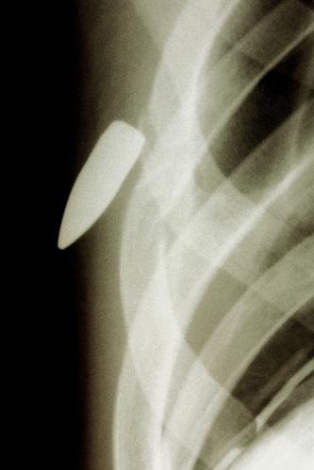

12879410891175362647.jpg

這張X照片展現了嵌入一位患者胸部的子彈。